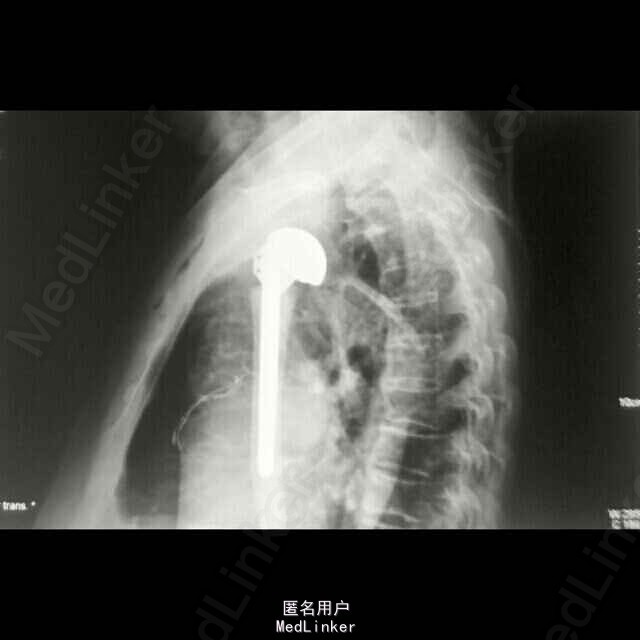

诊断:1、右侧人工肱骨头置换术后伴假体周围骨折 2、慢性肺气肿伴左侧胸腔积液 3、双侧脑基底节区陈旧性腔隙性脑梗塞灶 4、血压病(2级 高危层) 5、骨质疏松症(重度) 6、右髋关节置换术后 治疗: 因患者高龄,基础疾病较多,较重,故手术风险大,经呼吸内科,心血管内科及神经内科会诊及治疗处理后,患者内科病情控制稳定,予行手术治疗,术中检查,右肩关节假体无松动,故单纯予行假体周围骨折固定术治疗。

随访:术后1周指导患者功能锻炼,术后1月患肢功能基本恢复正常。讨论:患者系人工肩关节假体周围骨折,骨折远近段髓腔内填充有骨水泥,骨折端髓腔血运中断,故保守治疗效果欠佳,容易发生骨折多次移位,复位及固定困难,容易并发骨折延迟愈合,甚至不愈合,故应考虑积极手术治疗,早其有效固定骨折,并行局部植骨,有利于骨折生长及愈合;同时因患者右肱骨髓腔内骨水泥及金属假体填充,钻孔困难,钢板螺丝钉内固定术难度较大;同时不排除假体松动可能,故根据患者病情及具体情况,拟定手术方案:1、若假体松动,则行关节翻修,予更换加长柄假体,同时骨折部位记忆合金环抱器内固定;2、若术中假体无松动,则直接行“假体周围骨折切开复位记忆合金环抱器内固定术。